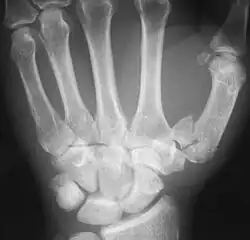

The first metacarpal bone or the metacarpal bone of the thumb is the first bone proximal to the thumb. It is connected to the trapezium of the carpus at the first carpometacarpal joint and to the proximal thumb phalanx at the first metacarpophalangeal joint.

The first metacarpal bone is short and thick with a shaft thicker and broader than those of the other metacarpal bones. Its narrow shaft connects its widened base and rounded head; the former consisting of a thick cortical bone surrounding the open medullary canal; the latter two consisting of cancellous bone surrounded by a thin cortical shell. [1]

Fractures

Fractures to metacarpal bones account for 30-40% of all hand fractures, of which 25% occur in the first metacarpal (second to fractures to the fifth metacarpal bone). 80% of fractures to the first metacarpal occur at its base. [6]

Common fractures to the thumb metacarpal include Bennett's fracture and Rolando's fracture